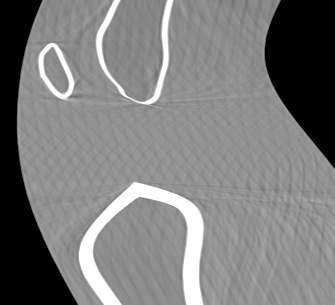

Involuntary subject motion is the main source of artifacts in weight-bearing cone-beam CT of the knee. To achieve image quality for clinical diagnosis, the motion needs to be compensated. We propose to use inertial measurement units (IMUs) attached to the leg for motion estimation. We perform a simulation study using real motion recorded with an optical tracking system. Three IMU-based correction approaches are evaluated, namely rigid motion correction, non-rigid 2D projection deformation and non-rigid 3D dynamic reconstruction. We present an initialization process based on the system geometry. With an IMU noise simulation, we investigate the applicability of the proposed methods in real applications. All proposed IMU-based approaches correct motion at least as good as a state-of-the-art marker-based approach. The structural similarity index and the root mean squared error between motion-free and motion corrected volumes are improved by 24-35% and 78-85%, respectively, compared with the uncorrected case. The noise analysis shows that the noise levels of commercially available IMUs need to be improved by a factor of $10^5$ which is currently only achieved by specialized hardware not robust enough for the application. The presented study confirms the feasibility of this novel approach and defines improvements necessary for a real application.